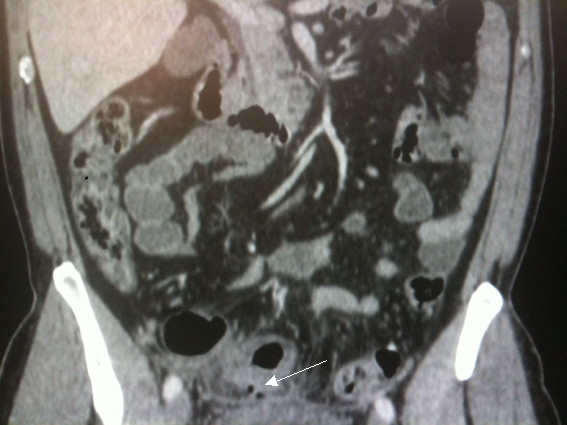

Figure 17 : Scanner abdominal objectivant une diverticulite.

La flèche montre deux diverticules au sein d'une paroi colique épaissie

(Copyright Dr D.Mennecier)

Cet examen permet aussi de définir la gravité de la diverticulite qui n'est pas obligatoirement associée à des signes cliniques bruyants. Ainsi le scanner abdominal diagnostique les formes sévères devant la présence d'un abcès voire de perforation par la présence d’air ou de produit de contraste extra- digestif.